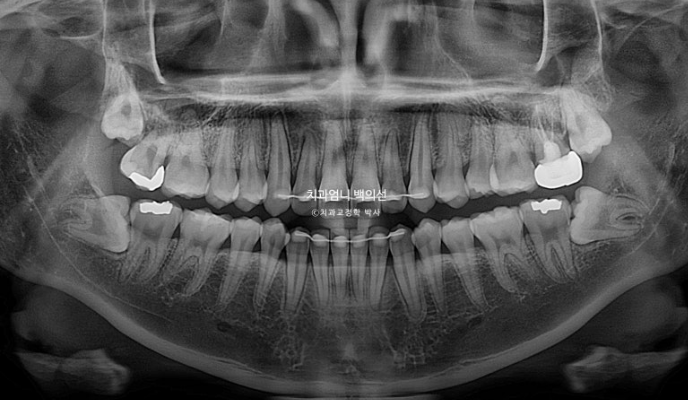

24.09

부분교정인만큼 치근흡수는 없고 뿌리 평행도도 양호합니다.